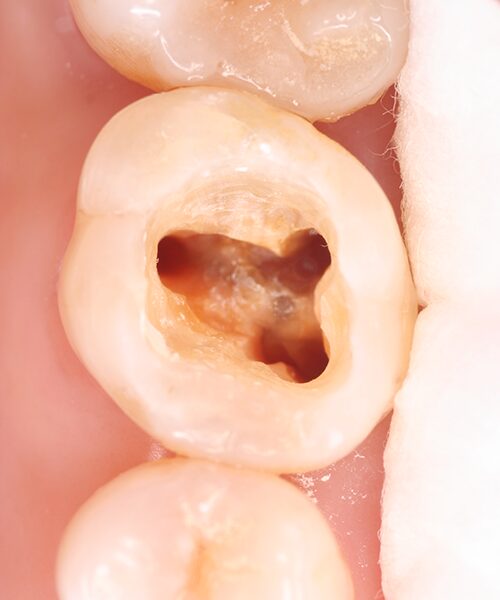

進行した虫歯や外傷によって歯髄が感染したり、壊死したりすると歯髄を取り除く「根管治療」が必要になります。これを一般的に「神経を抜く」と表現されています。

虫歯が進行し、歯髄にまで達すると歯髄炎となります。

炎症が正常な状態に回復しない場合(不可逆性歯髄炎)は抜髄などの根管治療が必要となります。

感染部分の除去

根管治療用の器具を使って、感染している歯質や残っている歯髄などを除去します。